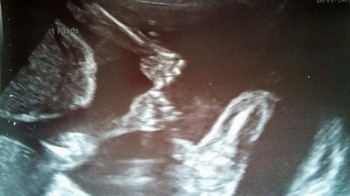

bayi kembar pegangan tangan di dalam rahim

rowan dan Blake di dalam rahim tampak berpegangan tangan. sumber: metro.co.uk

Hayley dibuat takjub karena setiap kali melakukan scan, ia melihat kedua bayinya sedang berpegangan tangan. Bayi kembar Hayley dilahirkan prematur secara caesar pada 25 Agustus 2016.